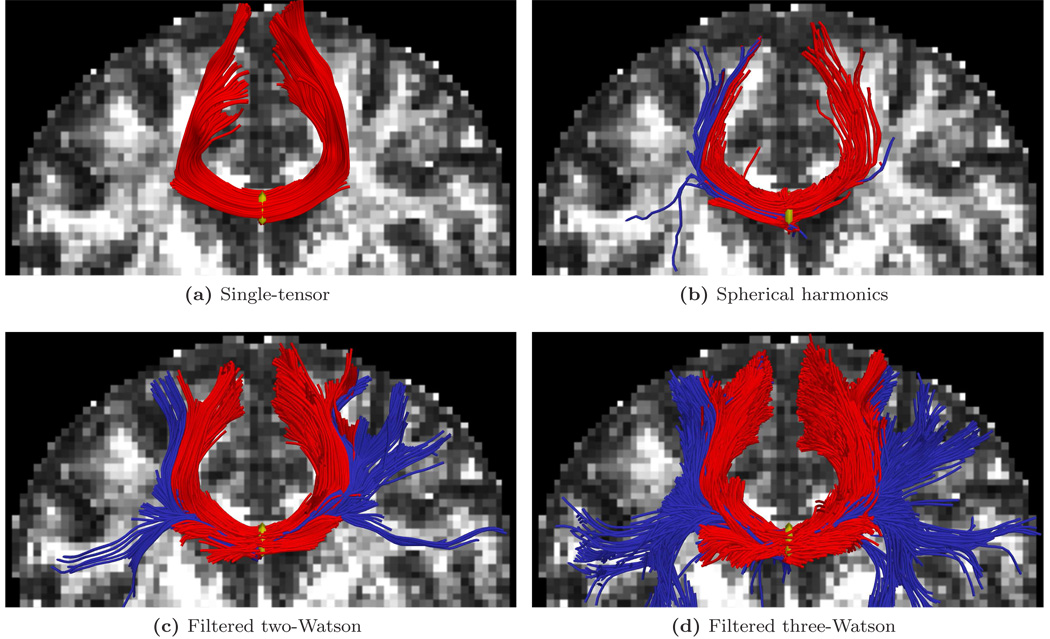

We first focused on fibers originating in the corpus callosum. Specifically, we sought to trace out the lateral transcallosal fibers that run through the corpus callosum out to the lateral gyri. It is known that single-tensor streamline tractography only traces out the dominant pathways forming the U-shaped callosal radiation (Fig. 9a and Fig. 15a). Several studies document this phenomena, among them the works of Descoteaux et al. [17] and Schultz and Seidel [46] have side-by-side comparisons. These fibers have been reported in using diffusion spectrum imaging [23], probabilistic tractography [32, 5, 17], and more recently with tensor decomposition [46].

Figure 9.

Filtered tractography picks up many fiber paths consistent with the underlying structures. Both single-tensor streamline and sharpened spherical harmonics are unable to find the majority of these pathways. Fibers existing ±22 mm around the mid-sagittal plane are indicated in blue. Seed region indicated in yellow.

Figure 15.

Tracing fibers originating from the center of the entire corpus callosum with views from above (top rows) and front-to-back (bottom rows). The proposed filtered tractography is able to find many of the lateral projections (blue) while single-tensor is unable to find any and few are found with sharpened spherical harmonics. Seed region indicated in yellow.

We start with two basic experiments: first examining the tracts surrounding a single coronal slice and second looking at all tracts passing through the corpus callosum. We seed each algorithm multiple times in voxels at the intersection of the mid-sagital plane and the corpus callosum. To explore branchings found using the proposed technique, we considered a component to be branching if it was separated from the primary component by less than 40° with k ≥ 0.6. Similarly, with sharpened spherical harmonics, we considered it a branch if we found additional maxima over the same range. We terminated fibers when the general fractional anisotropy of the estimated signal (std/rms) fell below 0.1. While such heuristics are somewhat arbitrary, we found little qualitative difference in adjusting these values.

To demonstrate the flexibility of the proposed filtering strategy with respect to model choice, we use both the two-Watson fiber model (Eq. 6) and the three-Watson fiber model (Eq. 7). While this introduced differences in the quantity of branchings detected, we found that using either model resulted in generally finding the same pathways.

For the first experiment, Fig. 9 shows tracts originating from within a few voxels intersecting a particular coronal slice. For a reference backdrop, we use a coronal slice showing the intensity of fractional anisotropy (FA) placed a few voxels behind the seeded coronal position. Keeping in mind that these fibers are intersecting or are in front of the image plane, this roughly shows how the fibers navigate the areas of high anisotropy (bright regions). Similar to the results in [17, 46], Fig. 9b shows that sharpened spherical harmonics only pick up a few fibers intersecting the U-shaped callosal radiata. In contrast, our proposed method traces out many pathways consistent with the apparent anatomy using either the two-fiber or three-fiber model. To emphasize transcallosal tracts, we color as blue those fibers exiting a corridor of ±22 mm around the mid-sagittal plane. Fig. 10 provides a closer inspection of Fig. 9c and Fig. 9d where, to emphasize the underlying anatomy influencing the fibers, we use as a backdrop the actual coronal slice passing through the voxels used to seed this run. Such results are obtained in minutes in our current Matlab implementation. At each step, the cost of reconstructing the signal for few sigma points approaches the cost of a few iterations of weighted least-squares estimation of a single tensor.

For the second experiment, Fig. 15 shows a view of the whole brain to see the overall difference between the different methods. Here again we emphasize with blue the transcallosal fibers found using the proposed filter. Comparing Fig. 15c and Fig. 15d we see several regions that appear to have different fiber density using the two models. This suggests that incorporating model selection into filtered approaches may have a significant effect. To show the various pathways infiltrating the gyri, Fig. 11 provides a closeup of the frontal lobe from above (without blue emphasis).